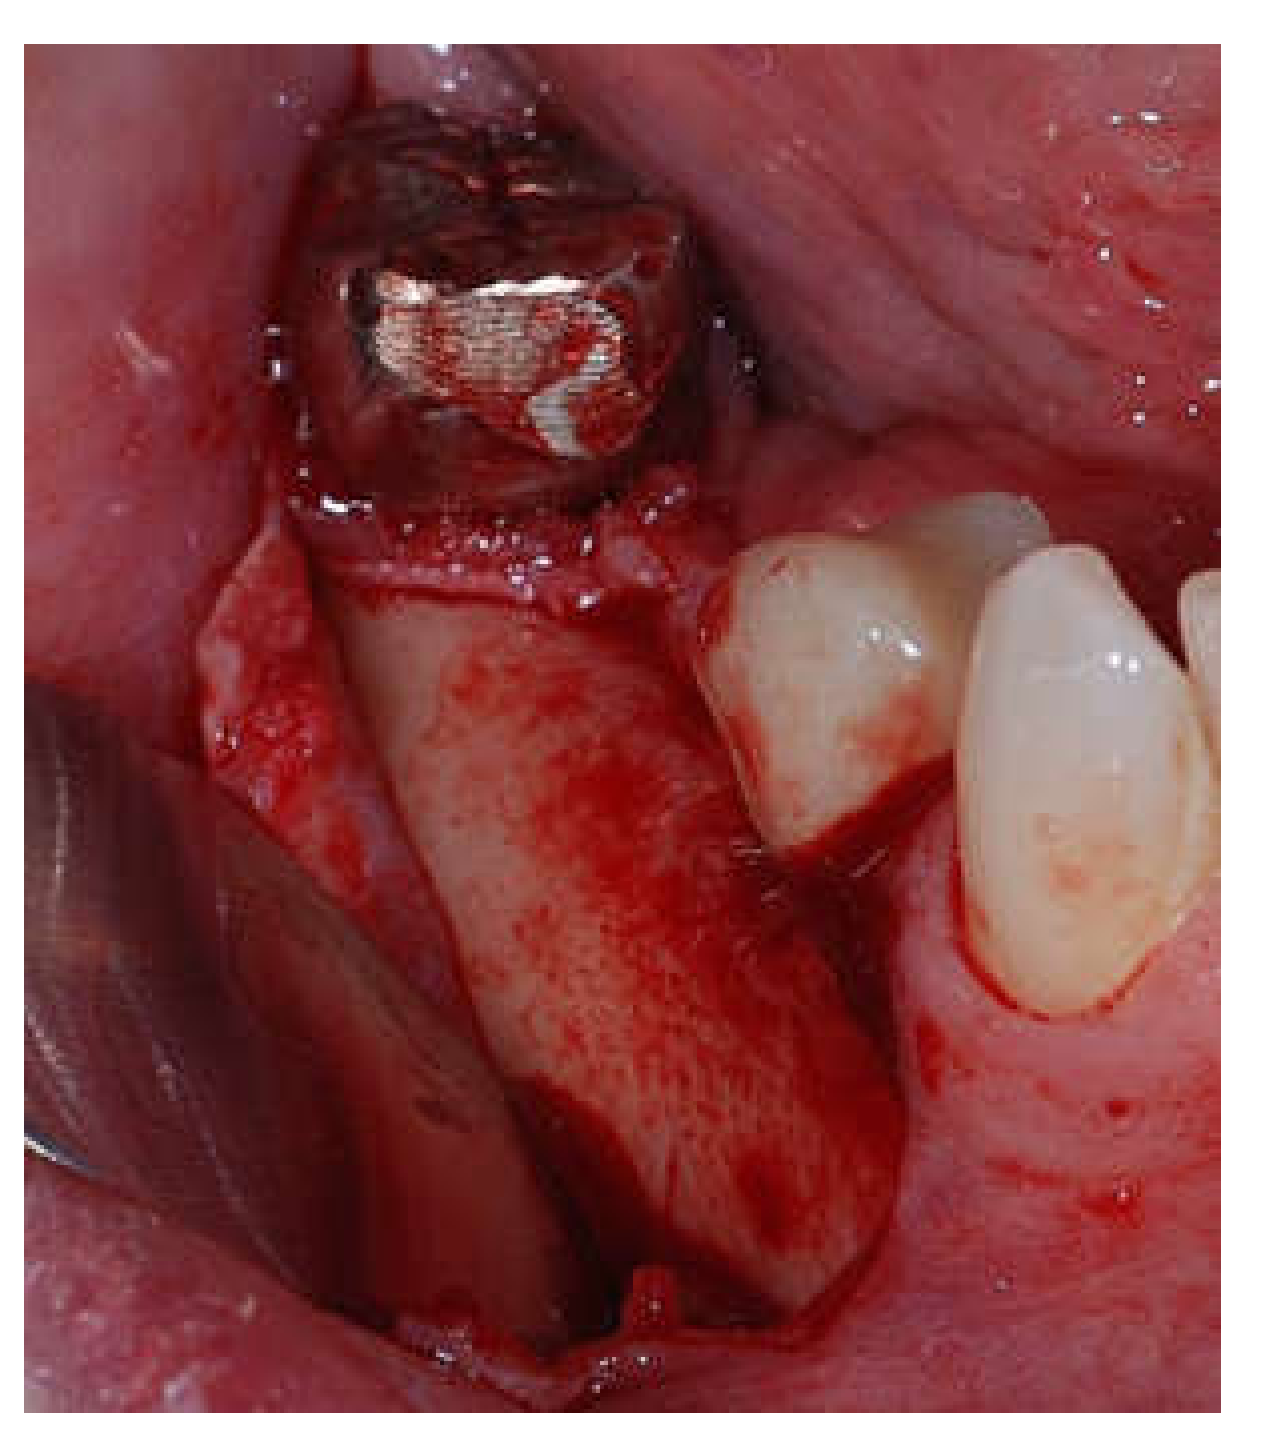

Clinical and CBCT aspects of patient from the test group, describing the stages of S-GBR technique and implant-prosthetic stage, are presented in Figure 1, Figure 2, Figure 3, Figure 4, Figure 5, Figure 6, Figure 7, Figure 8, Figure 9, Figure 10 and Figure 11. CBCT exam allows the evaluation of the horizontal alveolar bone defect and the position of the mandibular alveolar nerf (Figure 1A,B). Figure 1C,D show cross-sectional CBCT aspects of the implant sites. Figure 2 shows the narrowed mandibular alveolar bone with horizontal resorption. Figure 3 shows the exposed buccal surface of the alveolar ridge with severe horizontal resorption, after flap opening. The inserted implants (4.5 mm diameter, 11.5 mm length) and osteosynthesis screws (45° from the occlusal plan) are shown in Figure 4A. The placement of graft (autologous bone and xenograft) and collagen membrane is shown in Figure 4B. Figure 5A shows tension-free sutures, due to periosteal incisions alveolar ridge. Figure 5B shows clinical aspect at 7 months after surgery, with gingival tissue adherent on the reconstructed alveolar ridge. Figure 6 shows OPG aspect at follow-up of 7 months, with osseointegration of the dental implants. Figure 7A shows clinical aspect before osteosynthesis screws removal. Figure 7B shows clinical aspect after osteosynthesis screws removal. Figure 8A shows healthy peri-implant soft tissues. Figure 8B shows repositioning key for perfect position of abutments. Figure 10A,B show clinical aspects of implant-supported prosthetic restoration. Figure 11A,B show CBCT aspects of Osseo integrated dental implants at 24 months follow-up.

Figure 3.

Intra-operative clinical aspect after flap opening.